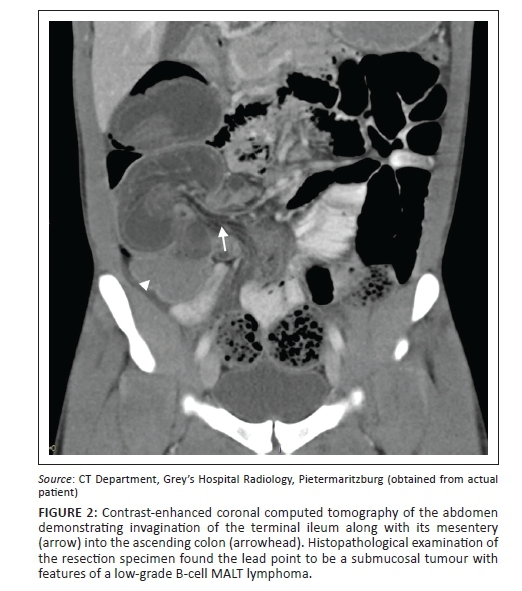

From www.gastrores.org